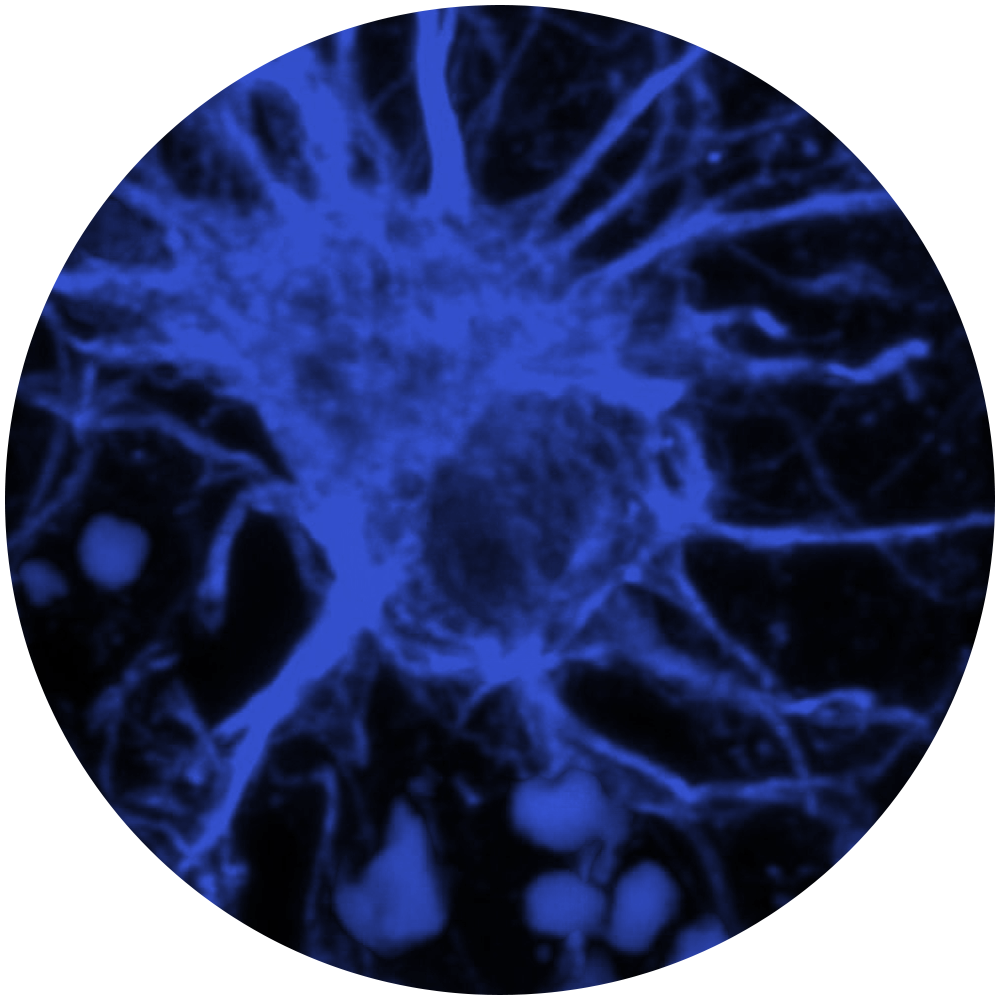

Our interdisciplinary team of investigators collaborated to tackle some of the most confounding and disabling medical conditions.

Our innovative discoveries are fueled by well-funded interdisciplinary collaborations. These partnerships accelerate the development of therapeutics and allow us to deepen our understanding of brain function and the processes that go awry in neurological diseases.

Gene therapies for neurological diseases